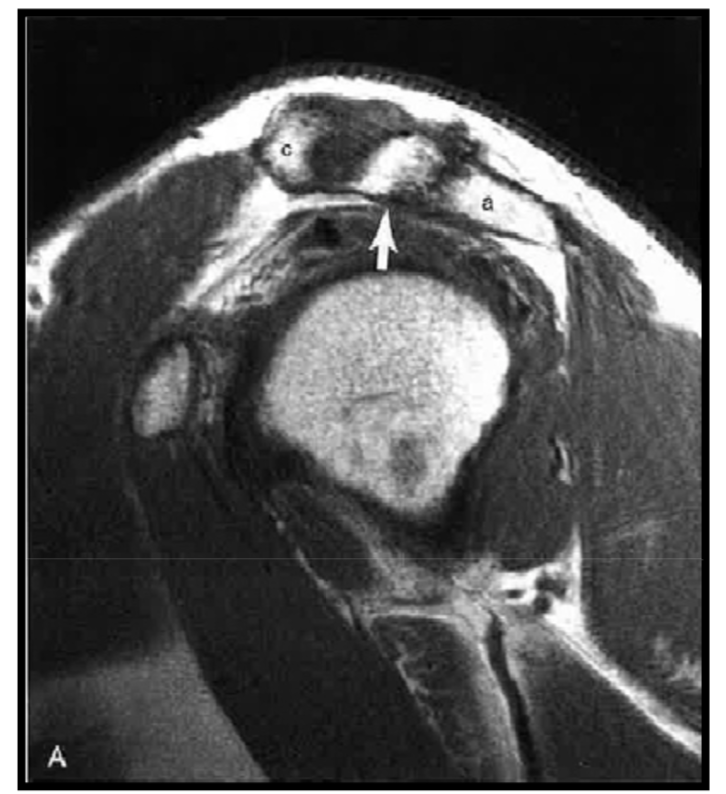

Acromial hook

variation anat normal